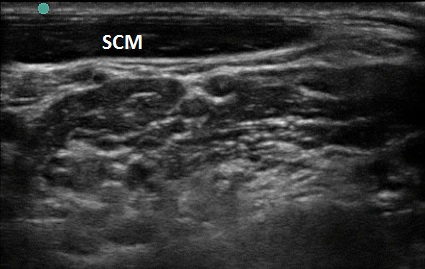

- Incomplete head rotation can place the SCM over the plexus and block the needle path. (Figure 5) Additional rotation will move the SCM muscle out of the path. (Figure 6)

Figure 5. SCM with improper head turn

Figure 6. SCM with proper head turn